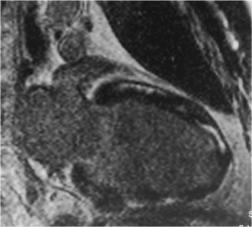

Рис. 7. МРТ сердца с отсроченным контра- |

стированием. |

Пациент М., ДКМП. Видны интрамиокардиальные |

очаги накопления КС линейной формы. |

Рис. 8. МРТ сердца.

Пациент С., АДПЖ. а – Кино-МРТ, короткая ось ЛЖ. Определяется истончение передней стенки ПЖ, мелкие участки выбухания. б – Отсроченное контрастирование передней стенки ПЖ на всем протяжении.